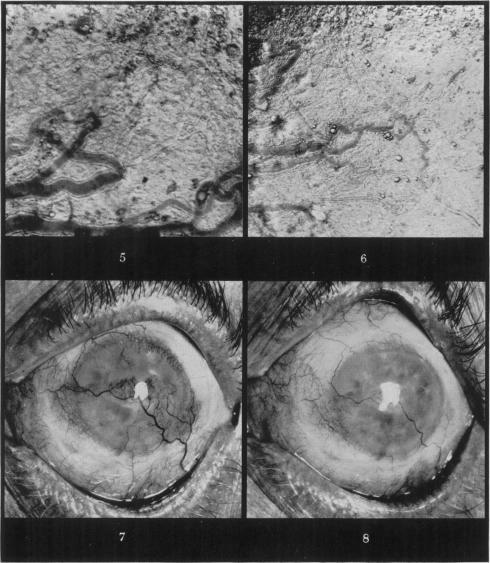

In vivo observations of the effects of cortisone upon the blood vessels in rabbits ear chambers.

Br J Exp Pathol. 1952 Oct;33(5):445-50.